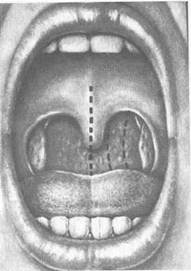

Рис. 3.19. Гиперкератоз глотки.

К гипертрофическим формам фарингита относится гиперкератоз миндалин, при котором на поверхности лимфаденоид-ной ткани глотки образуются пирамидоподобные остроконечные выросты ороговевшего эпителия размером около 2—3 мм. Чаще всего желтовато-белые плотные образования выступают на зевной поверхности небных миндалин, сосочках языка (рис. 319). Они отличаются от лакунарных пробок твердостью и прочной спаянностью с эпителием, с трудом отрываются пинцетом. Морфологически характеризуются пролиферацией эпителия с ороговением.

При микроскопическом исследовании в этих образованиях обнаруживают нитчатые бактерии В. leptotrix, что дает основание считать данный возбудитель этиологическим фактором в возникновении заболевания. Процесс протекает хронически и долгое время остается не обнаруженным из-за отсутствия воспаления тканей и клинических проявлений, еле Н°3 устанавливают ПРИ осмотре и гистологическом ис-^ Довании эпителиальных выростов. Специфической терапии гт^УЩесТвует- Нри сопутствующем хроническом тонзиллите "оказана тонзиллэктомия.